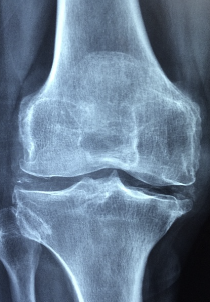

관절엔 콘드로이친 1200mg 콘드로이친 효능 및 부작용에 대해 알아보도록 하겠습니다. 콘드로이친은 관절 연골의 주요 구성 요소인 그리코사민과 콘드로이틴의 합성을 촉진시키는 물질입니다. 연골은 뼈와 뼈 사이에서 충격을 흡수하고 관절의 움직임을 도와주는 역할을 합니다. 특히 연령이 들어가면서 연골 조직이 파괴되는 연령관련 관절염이나 스포츠 부상 등으로 인한 연골 손상을 예방하고 치료하는 데 도움이 됩니다. 콘드로이친은 연골 세포의 생산성을 증가시키고 연골 조직을 보호하면서 연골 손상을 감소시키는 데 효과적입니다. 또한 관절 염증을 감소시키고 관절 건강을 유지하는 데도 도움이 됩니다. 콘드로이친은 일반적으로 관절 건강에 좋은 영양제로 사용되며, 식이 보충제나 음식에서 쉽게 얻을 수 있습니다. 하지만 사용전 의사와 상담하고 지정된 권장 섭취량을 지켜야 합니다.

콘드로이친은 연골 손상이나 연골염 등으로 인한 관절통을 완화하는 데 도움이 되는 성분입니다. 이 성분은 연골 조직의 구성성분 중 하나인 그리코사민을 생성하기 위해 필요한 원료로 작용하며, 연골 세포의 생산성을 높여 염증을 줄이고 뼈 건강에도 좋은 영향을 줍니다. 또한, 콘드로이친은 스포츠 재활 프로그램에서도 사용되며, 관절염이나 골다공증 등의 질환 예방에도 도움이 됩니다. 연구에 따르면 콘드로이친은 통증 완화와 함께 기능적 측면에서도 이점을 제공하며, 오랜 기간 안전하게 복용될 수 있습니다. 하지만 콘드로이친은 항응고제와 상호작용하므로, 항응고제를 복용하는 환자들은 의사와 상의한 후 복용해야 합니다.